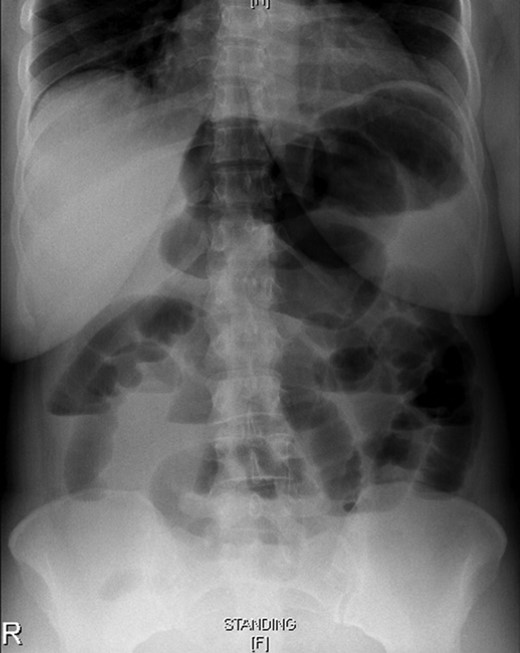

Laboratory investigations, including a complete blood count, urea and analysis, and coagulation profile, were all within normal limits. An abdominal X-ray showed a dilated large bowel with few air fluid levels, no gas in the rectum and no air under the diaphragm (Fig. 1). An abdominal CT scan with oral and intravenous contrast showed that the cecum was flipped superiorly and positioned anteriorly to the transverse colon, and it herniated into the foramen of Winslow (opening between the inferior vena cava and portal vein). The cecum occupied the lesser sac, and it was distended with gas and caused a mass effect on the stomach and hepatic root, with associated intrahepatic bile duct dilatation. This was associated with proximal small bowel dilatation and collapsed large bowel loops distally (Fig. 2). These findings were consistent with an obstructive internal hernia into the lesser sac through the foramen of Winslow.

Erect abdominal X-ray showing proximal small bowel dilatation with multiple air fluid levels suggestive of bowel obstruction.